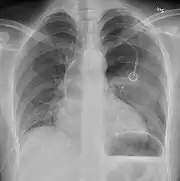

Chest X-ray

A plain chest radiograph, ideally with the X-ray beams being projected from the back (posteroanterior, or "PA"), and during maximal inspiration (holding one's breath), is the most appropriate first investigation.[30] It is not believed that routinely taking images during expiration would confer any benefit.[31] Still, they may be useful in the detection of a pneumothorax when clinical suspicion is high but yet an inspiratory radiograph appears normal.[32] Also, if the PA X-ray does not show a pneumothorax but there is a strong suspicion of one, lateral X-rays (with beams projecting from the side) may be performed, but this is not routine practice.[15][19]

Chest X-ray showing a pneumothorax on the right (left in the image), where the absence of lung markings indicates that there is free air inside the chest

It is not unusual for the mediastinum (the structure between the lungs that contains the heart, great blood vessels, and large airways) to be shifted away from the affected lung due to the pressure differences. This is not equivalent to a tension pneumothorax, which is determined mainly by the constellation of symptoms, hypoxia, and shock.[13]

The size of the pneumothorax (i.e. the volume of air in the pleural space) can be determined with a reasonable degree of accuracy by measuring the distance between the chest wall and the lung. This is relevant to treatment, as smaller pneumothoraces may be managed differently. An air rim of 2 cm means that the pneumothorax occupies about 50% of the hemithorax.[15] British professional guidelines have traditionally stated that the measurement should be performed at the level of the hilum (where blood vessels and airways enter the lung) with 2 cm as the cutoff,[15] while American guidelines state that the measurement should be done at the apex (top) of the lung with 3 cm differentiating between a "small" and a "large" pneumothorax.[33] The latter method may overestimate the size of a pneumothorax if it is located mainly at the apex, which is a common occurrence.[15] The various methods correlate poorly but are the best easily available ways of estimating pneumothorax size.[15][19] CT scanning (see below) can provide a more accurate determination of the size of the pneumothorax, but its routine use in this setting is not recommended.[33]

Not all pneumothoraces are uniform; some only form a pocket of air in a particular place in the chest.[15] Small amounts of fluid may be noted on the chest X-ray (hydropneumothorax); this may be blood (hemopneumothorax).[13] In some cases, the only significant abnormality may be the "deep sulcus sign", in which the normally small space between the chest wall and the diaphragm appears enlarged due to the abnormal presence of fluid.[16]